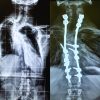

A 33-year-old woman visited our hospital due to neck pain and cervical kyphotic deformity. She had a history of NF-1 and her neurological findings were normal at her first visit. X-ray of the cervical spine showed severe wedged deformity of the vertebral body at the C3 and C4 levels and the kyphotic angle was 56° (Fig. 1a). Magnetic resonance imaging of the spine showed neither spinal cord compression nor spinal cord tumor (Fig. 1b). We performed the initial surgery of O-T2 posterior spinal fusion after halo traction for one week (Fig. 2). We then performed the second surgery of anterior spinal fusion from C3 to C6 using an autologous vascularized fibular graft 3 weeks after the initial surgery. After performing corpectomy of the C4 and C5 vertebral bodies, the vessels of the fibular graft were anastomosed to the superior thyroid artery and vein under a microscope. The cervical kyphotic angle improved from 56° to 0° on X-ray (Fig. 3a and b).

We placed the patient in a halo vest for 1 month and additionally started teriparatide treatment 20 µg/day for coexisting bone fragility 1 week after the second surgery. Follow-up computed tomography (CT) 3–7 months after surgery demonstrated a trend toward bony fusion and partial bony fusion of the grafted fibula, respectively (Fig. 4a and b). Furthermore, CT findings showed complete bony fusion 12 months after surgery (Fig. 4c). Seven years after the surgery, her neurological condition was normal despite slight neck stiffness and cervical spine X-ray showed maintenance of alignment immediately after surgery (Fig. 5). In the present case, complete bony fusion was achieved within 12 months after two-stage circumferential spinal fusion using an autologous vascularized free fibula and teriparatide administration. The rate of non-union after spinal fusion is high in NF-1, especially dystrophic NF-1 [4,8]. A vascularized fibular graft is recognized as an option for the surgical management of NF-1-associated cervical kyphosis. Asazuma et al. performed anterior and posterior spinal fixation for a patient with cervical kyphosis induced by neurofibromatosis. They used a vascularized free fibula for anterior fixation, which resulted in complete bone fusion [9], whereas Saika et al. reported that bone union was not achieved in 30% of the patients who underwent anterior spinal fusion surgery even when a vascularized fibular graft was used [10]. We also used a vascularized free fibula in the anterior surgery of the present patient following posterior instrumented fusion and obtained complete anterior fusion, but we additionally started teriparatide treatment for bone fragility after the two-stage surgery. Recently, it has been reported that teriparatide promotes fusion in spinal fusion surgery [11] and fracture healing [7,12]. Lehman et al. showed that the histologic intertransverse process fusion rate differed significantly between the teriparatide group and controls (86.7% vs. 50%) in a rabbit model [13]. Furthermore, Sugiura et al. also reported that teriparatide enhanced bone healing and bone fusion in rats [14]. In humans, the use of teriparatide has a positive effect on improving the rate of bone fusion. Seki et al. demonstrated the advantages of teriparatide for bone fusion after surgery for adult spinal deformity in osteoporotic patients [11]. Ohtori investigated the effect of teriparatide on bone fusion after lumbar spinal fixation. The bone fusion rate was greater in the teriparatide group than in the bisphosphonate group (82% vs. 68 %) [6]. Furthermore, the mean time to fusion was shorter in the teriparatide group than in the bisphosphonate group (8 vs. 10 months) [6]. In the present study, we administered the teriparatide for bone fragility after spinal fusion for NF-1-associated cervical deformity and obtained complete bony fusion, although we also used an autologous vascularized fibular graft to promote bone fusion. We speculate that not only the use of a vascular fibular graft but also the administration of teriparatide for bone fragility may be associated with complete fusion after surgery based on the findings of the previous studies concerning the effect of teriparatide on spinal fusion.